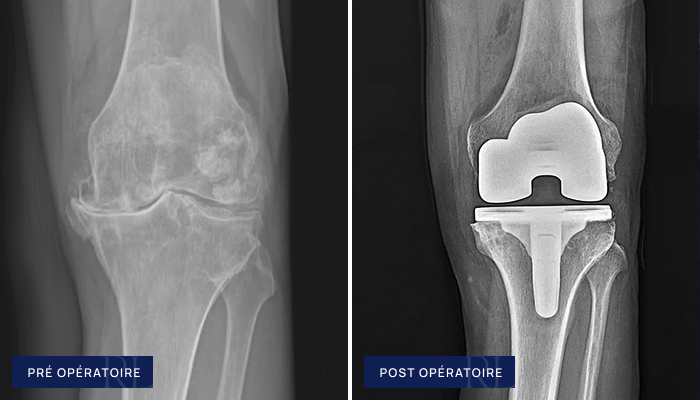

Gonarthrose (Prothèse unicompartimentale – PUC)

À gauche : Usure localisée du cartilage du genou (gonarthrose interne isolée)

À droite : Mini prothèse interne (Prothèse unicompartimentale avec guide de coupe sur mesure)